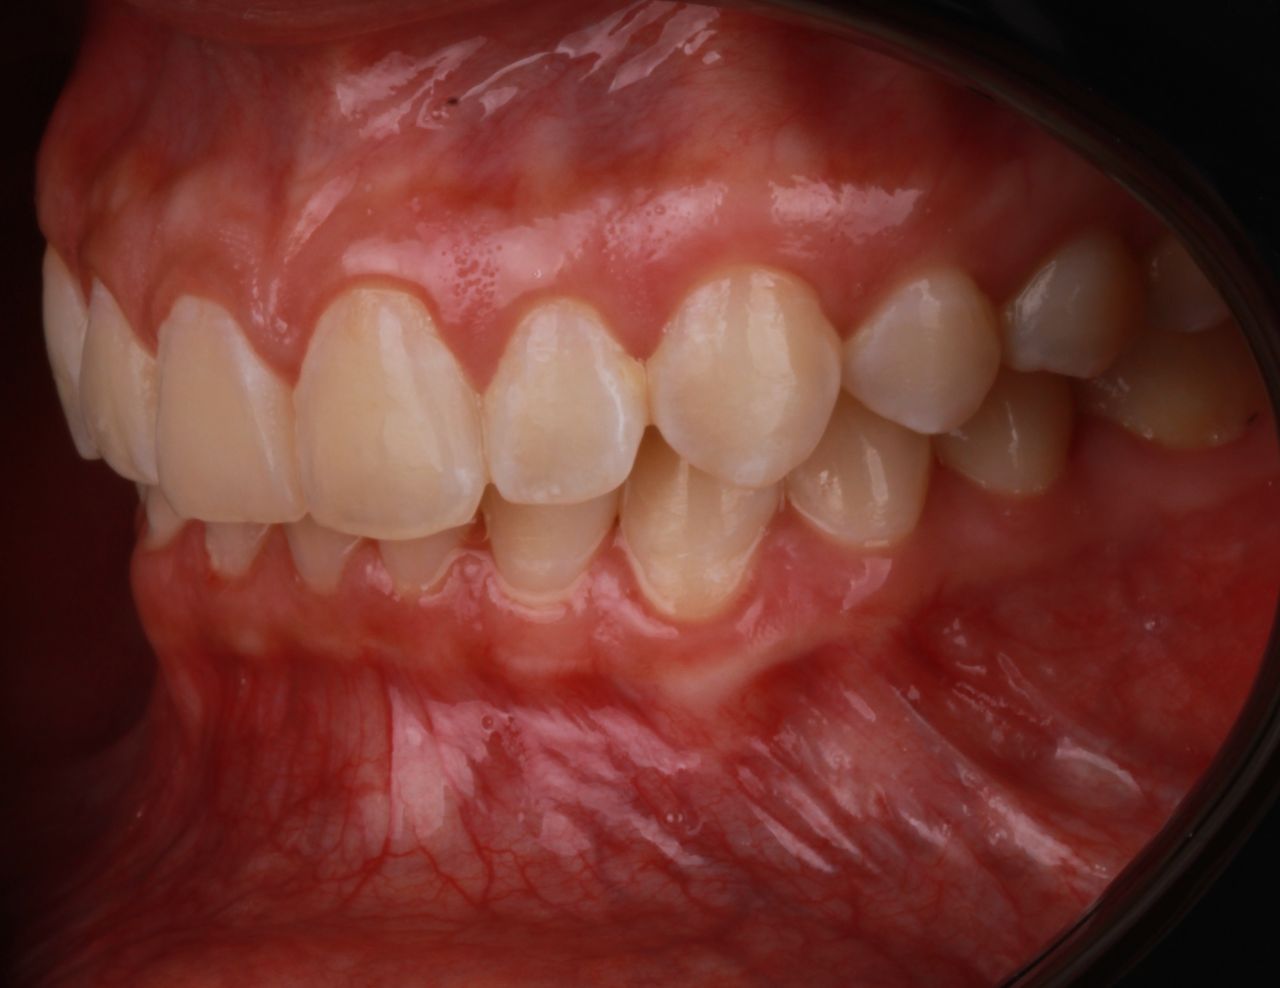

La especialidad en prótesis Bucal se enfoca en rehabilitar mediante prótesis unitarias, múltiples o totales la función masticatoria de nuestros pacientes brindándoles una mejor estética dental, confort, anatomía dental y función.

La evaluación es integral y multidisciplinaria, teniendo como objetivo una atención humana de calidad, ética, profesionalismo y calidez